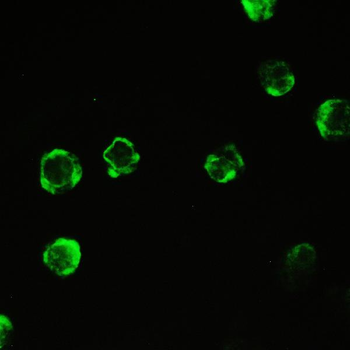

Anti-Cyclophilin A/PPIA Antibody [orb19174]

FC, ICC, IF, IHC, IHC-Fr, WB

Human, Mouse, Rat

Rabbit

Polyclonal

Unconjugated

10 μg, 100 μgCYPA Rabbit Polyclonal Antibody [orb100498]